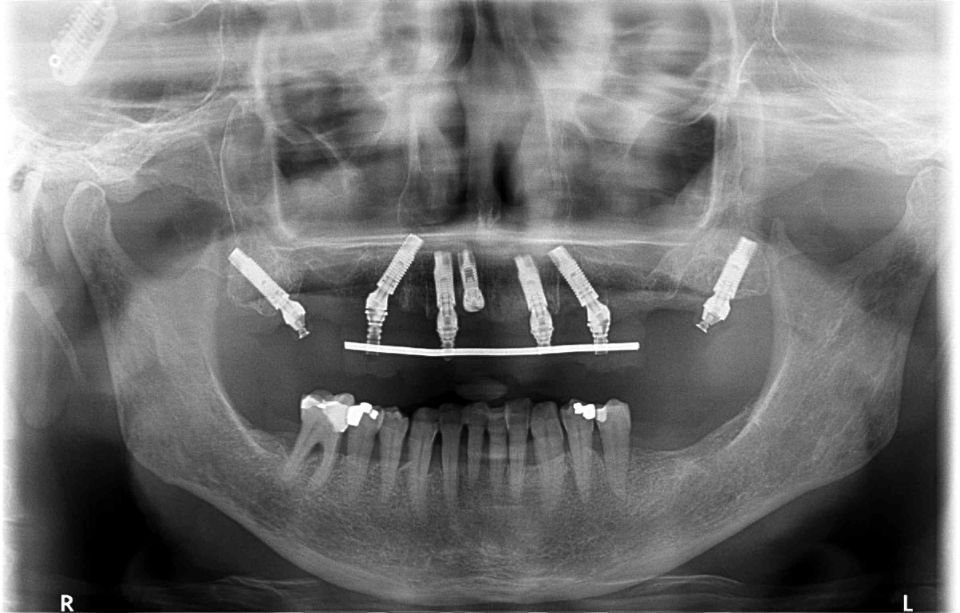

Radiodiagnòstic

El Centre Odontològic Piñera disposa d´un equip radiològic d´última generació que permet fer Ortopantomografies (radiografies de tota la boca), CBCT dental i escàner dental intraoral en 3D (3 dimensions). L?exposició radiològica és mínima.

Aquesta tecnologia afavoreix la rapidesa en l'exploració, així com la precisió en el diagnòstic i el tractament consegüent.

També tenim un equip de RX per fer radiografies intraorals.